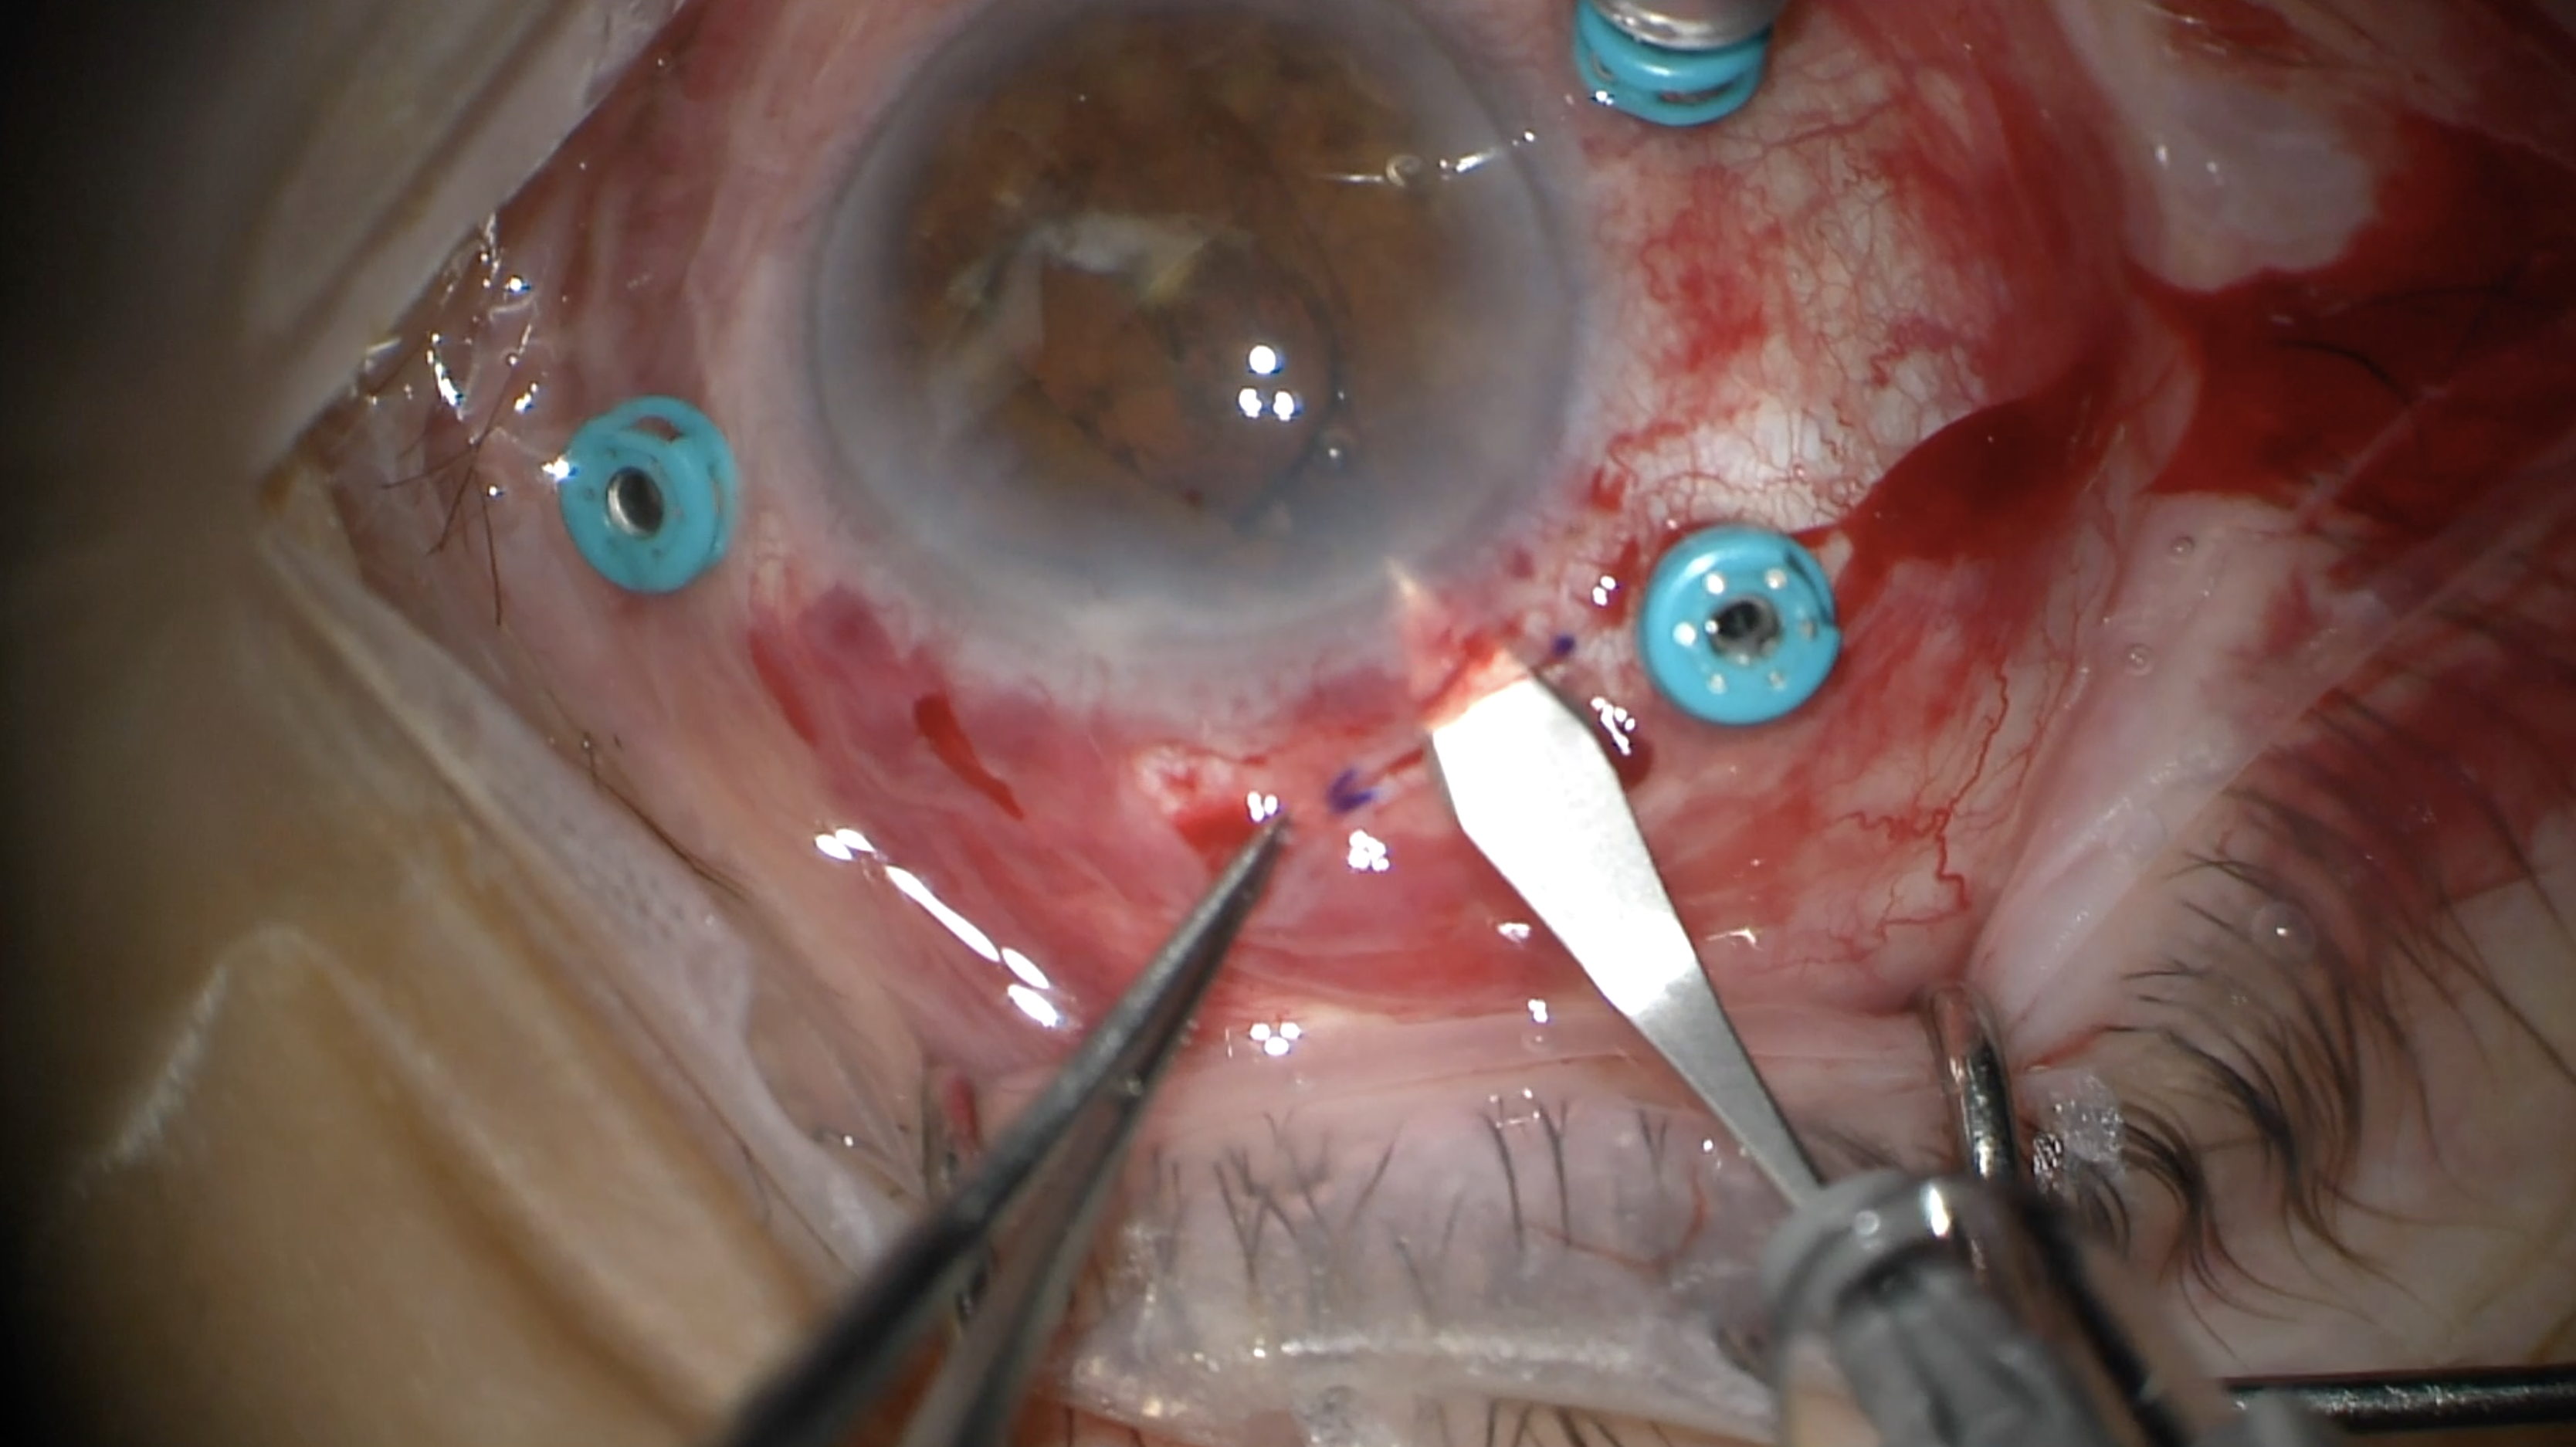

Epiretinal Membrane Peel Post IOFB

Original Contributor(s): Hasenin Al-khersan, MD; Kenneth C. Fan, MD, MBA

Presenter/Faculty: Al-khersan, Fan